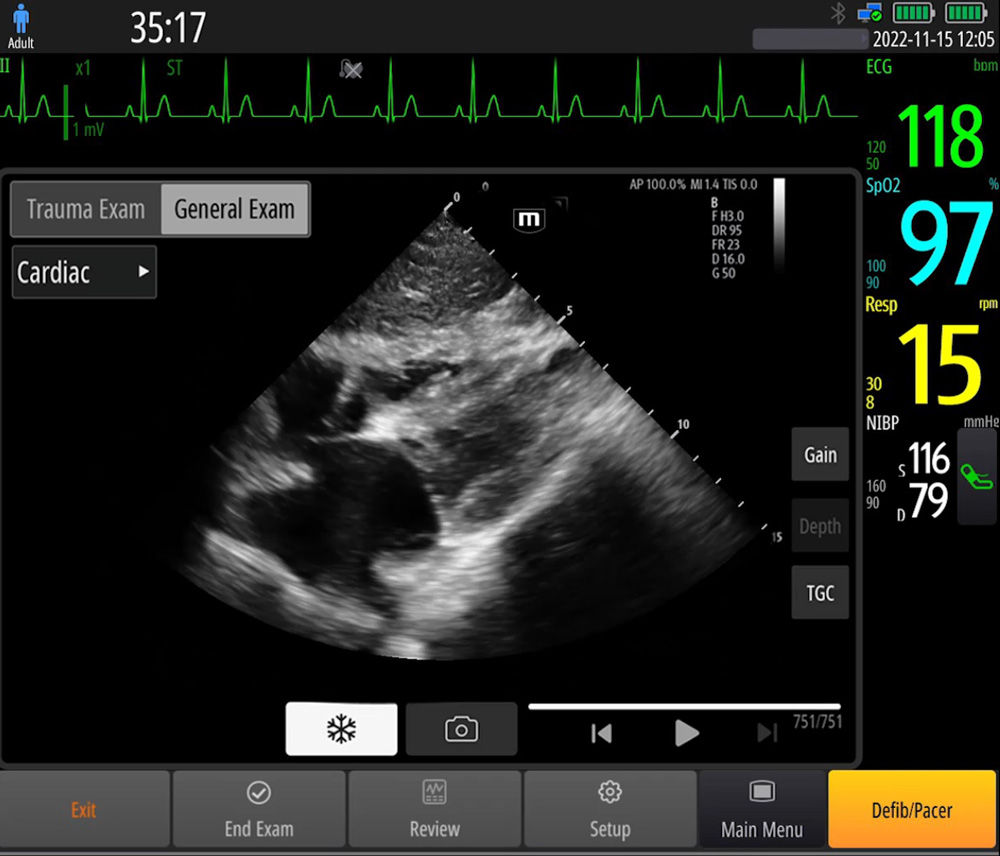

Bak?m Noktas? Ultrasonu (POCUS)

Entegre ultrason fonksiyonlar?, yerinde tan? i?in destek sunar ve uygulamay? tamamen gÞ?lÞ hale getirmek i?in ak?ll? ?al??ma k?lavuzu sa?lar.

- Referans g?rÞntÞler ve Kullan?m k?lavuzlar?

- A?amal? dizi probu: yÞksek ??zÞnÞrlÞk, yayg?n kullan?m